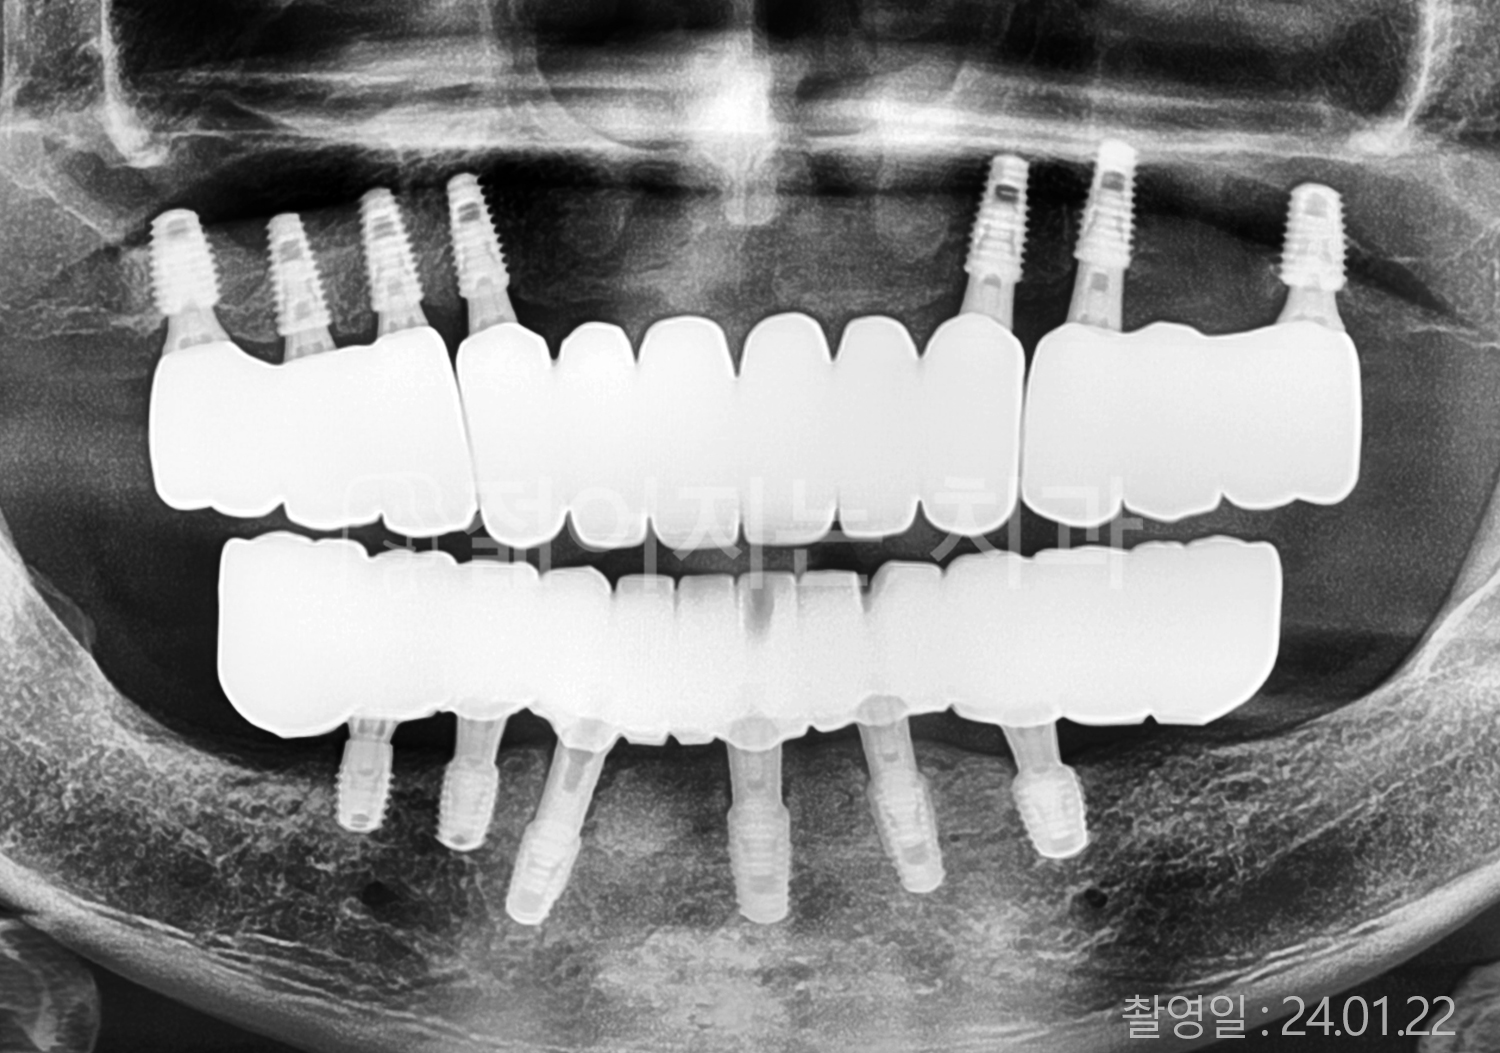

• 80대 전체치아 10개 이상 임플란트

• 60대 고혈압, 당뇨, 고지혈증 전체치아 10개 이상 임플란트

• 60대 전체치아 10개 이상 임플란트

• 60대 고혈압, 고지혈증 전체치아 10개 이상 임플란트

• 50대 고혈압, 당뇨, 고지혈증 전체치아 10개 이상 임플란트

• 70대 골다골증, 파킨스병 전체치아 10개 이상 임플란트

• 40대 전체치아 10개 이상 임플란트

• 60대 골다골증 전체치아 10개 이상 임플란트

• 40대 고혈압 전체치아 10개 이상 임플란트

• 50대 전체치아 10개 이상 임플란트

• 70대 전체치아 10개 이상 임플란트